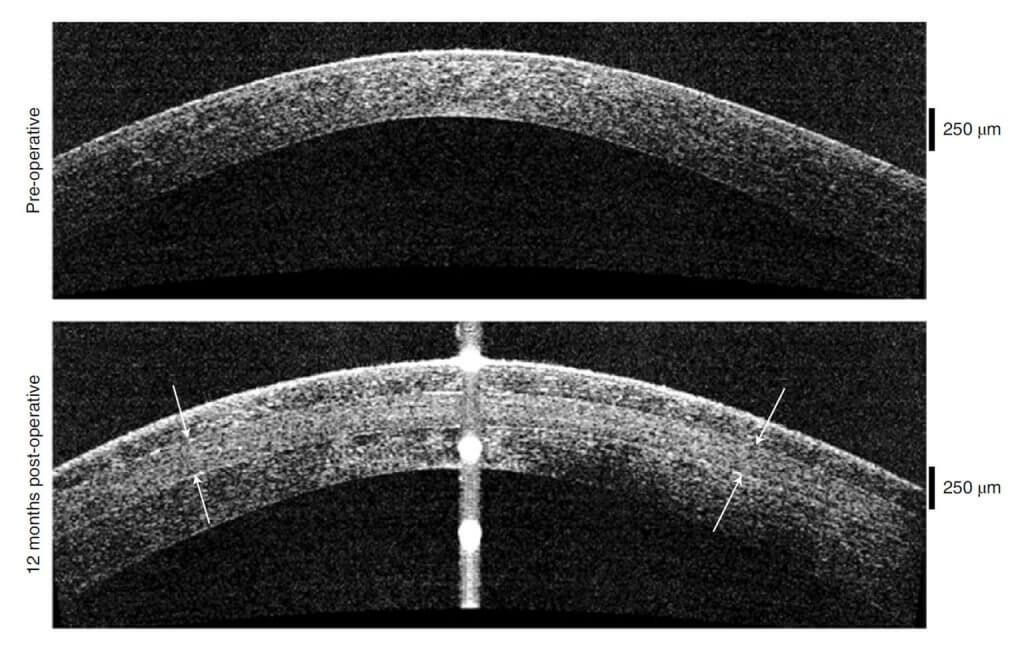

Después de dos años, los participantes de Irán e India experimentaron un aumento promedio de más de 200 micrómetros en el grosor de su córnea y una disminución en su curvatura, mejorando su visión al menos en la medida de los trasplantes de córnea tradicionales.